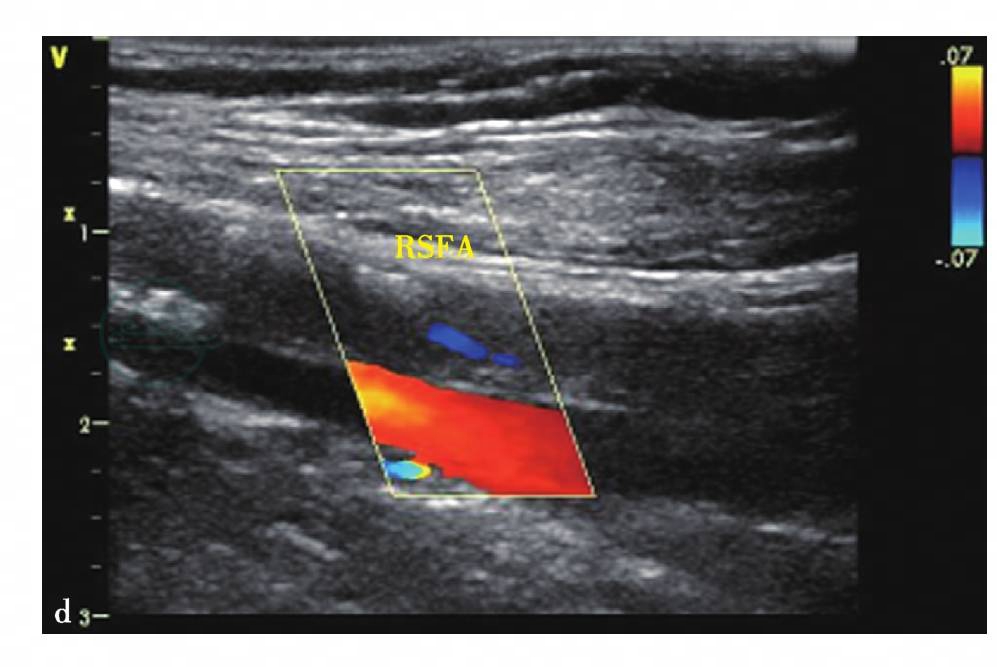

图11 d,右股浅动脉彩色超声多普勒图像示右侧股浅动脉管腔内充盈缺损大于90%,相应管腔明显变窄,仅见纤细血流显示(蓝色血流),伴随股静脉充盈良好